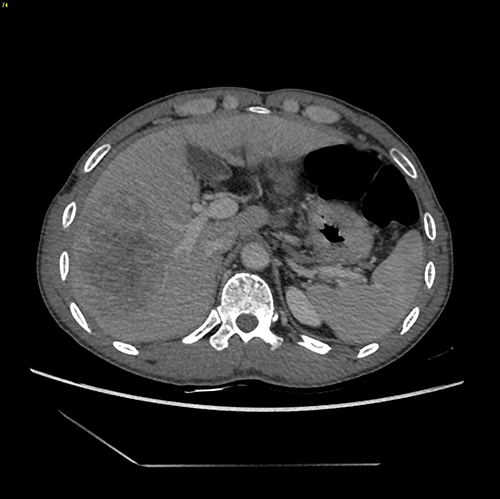

右肝癌----右肝部分切除